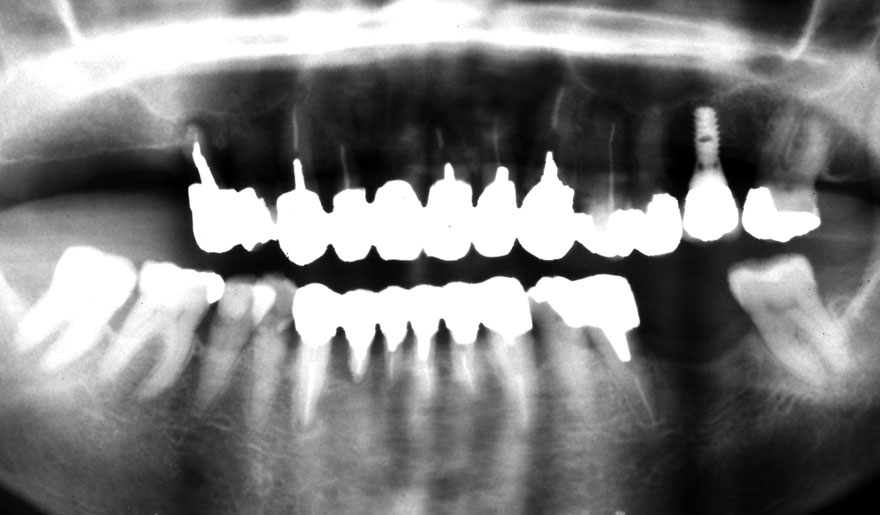

初診時 51歳 男性 平均歯槽骨喪失量:2.83mm

河田歯科医院

21年後 72歳

平均歯槽骨喪失量:2.51mm

21年間再生量:+0.32mm

年間再生速度:+0.015mm

(ケア頻度:1.20ヵ月ごと)